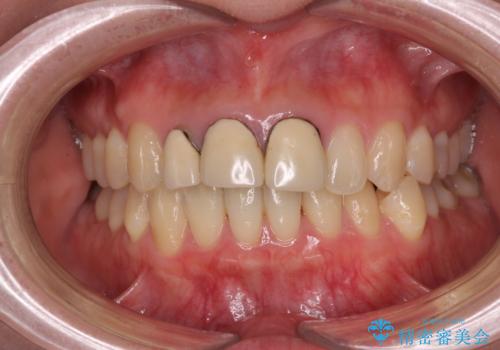

前歯の黒い縁を綺麗にしたい 前歯のオールセラミック

金属を除去したことで、周りと調和した自然な色合いとなり、クラウンの際の位置も歯肉に少し入り込む位置となっているためまるで本物の歯のような仕上がりとなりました。